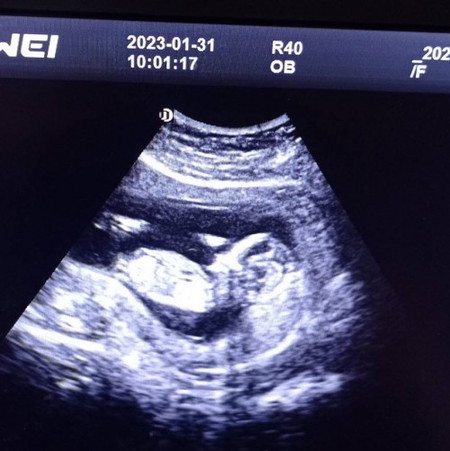

อยากทราบเพศน้อง

แม่ๆพอจะมองออกมั้ยคะว่าน้องเป็นผู้ชายหรือผู้หญิง คุณหมอบอกว่าน้องเป็นผู้หญิงค่ะ แต่แม่อยากได้ความมั่นใจเพิ่มค่ะ เพราะทางนี้อยากได้ผู้หญิงมากๆค่ะ

ในภาพไม่เห็นค่ะ เป็นภาพจากด้านข้างน้อง ไล่จากขวาคือหัว ลำตัว ขา

ต้องรอให้อายุครรภ์มากกว่านี้ถึงจะชัด ตอนนี้ยังดูไม่ออกเลยคะ

หรอคะ เดี๋ยวรอบหน้า ขอรูปหมอใหม่ค่ะ หมอบอกว่าถ้าเป็น ผู้ชายจะเห็นแหลมๆตั้งแต่12-13 วีคค่ะ เพราะน้องอ้าขาให้หมอเห็นอ่ะค่ะ